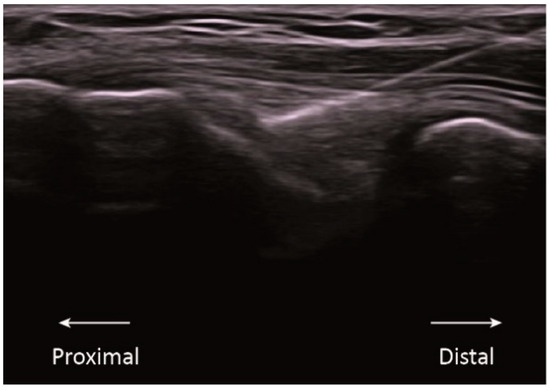

The high-intensity group had the needle inserted without current for 75 s. After this time, three galvanic current pulses were applied with an intensity of 3 mA and a duration of 3 s each one, with 3 s of rest between them, resulting in a 90 s intervention duration. This PE modality was employed by López-Martos et al. [11] and Moreno et al. [3] studying the PE effects (Figure 2A).

Figure 2.

Study methodology illustration. (A) The needle intervention, the three PE protocols application, and the representation of the intensity variation through the intervention duration depending of the PE group. (B) The outcomes assessment timeline, location, and methodology applied. PPT, Pressure Pain Threshold; CPM, Conditioned Pain Modulation; and TS, Temporal Summation.